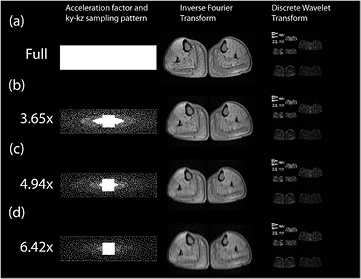

Critically the purpose to which the images with compressed sensing images are put will determine the maximum acceleration. In the case of the reconstructed CS-PI muscle images shown in figure 9, the images appear qualitatively equivalent, though with increasing acceleration, there is some loss of high frequency features (such as minor fasciae), which make the muscle groups harder to differentiate. The data were acquired for the purpose of monitoring fat content in particular muscle groups and two independent observers concurred that a 5× acceleration was the maximum compatible with defining all the desired muscle groups (Hollingsworth et al 2014). However, had only the total muscle volume been desired then the 6.42× acceleration acquired (and possibly higher accelerations) would also have been acceptable.

Figure 9. Examples of combined compressed sensing and parallel imaging reconstructions of fat fraction maps for the calf muscle of a subject with Becker muscular dystrophy. The figure compares full Nyquist sampling with accelerations performed using variable density Poisson disk acquisitions at 3.65×, 4.94× and 6.42×. The reconstruction quality is found to be very good: in the broader series, some muscle groups cannot be segmented on the 6.42× acceleration images (Hollingsworth et al 2014).

Download figure:

Standard image High-resolution imageWhere the endpoints to be extracted are quantitative, it is possible to construct Bland–Altman analyses to compare the measurements from the accelerated images with those from conventional acquisition (Vincenti et al 2014, Loughran et al 2015, Mann et al 2015). According to the precision with which we wish to make the measurement and the segmentation required of the image, we can define the maximum acceleration.

Alternatively, if we are mainly concerned with visual fidelity, metrics such as the structural similarity index (Wang et al 2004) can be evaluated for increasing acceleration if we have both the fully sampled and the accelerated images (Hollingsworth et al 2014), or the parameters of a blurring filter (such as the full width half maximum of a Gaussian blurring kernel) (Ajraoui et al 2013). It may then be possible to define a lower bound of acceptability using such a metric. Much work remains to be done to generalize these findings.

The MR imaging forms but one part of very intense trials, where there is interest in a wide coverage of skeletal muscle, and often also of the heart, meaning that the burden of the MRI to often very young (5–10 year old) patients is substantial. Combined compressed sensing and parallel imaging MRI has been applied in subjects with Becker muscular dystrophy to achieve scan accelerations up to 5× over conventional fat fraction measurements (figure 9) to achieve full volumetric muscle coverage within a 1 min scan (Loughran et al 2015). Importantly it has been demonstrated that the adjustable parameters of the compressed sensing reconstruction are identical for a given undersampling pattern and acceleration, which means that these parameter values can be confidently used in the absence of fully sampled data. The image quality produced with a fivefold acceleration allows two observers to confidently delineate the muscle regions of interest used for analysis (Hollingsworth et al 2014).